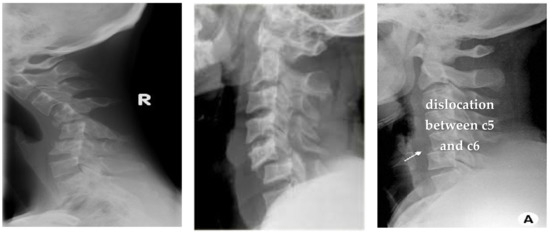

4.1.2. Clinical Case Study